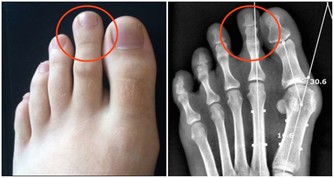

- 腕管綜合症:反覆使用手腕或長期握持物品可能引發腕管內神經受壓,出現手部麻木及刺痛感。